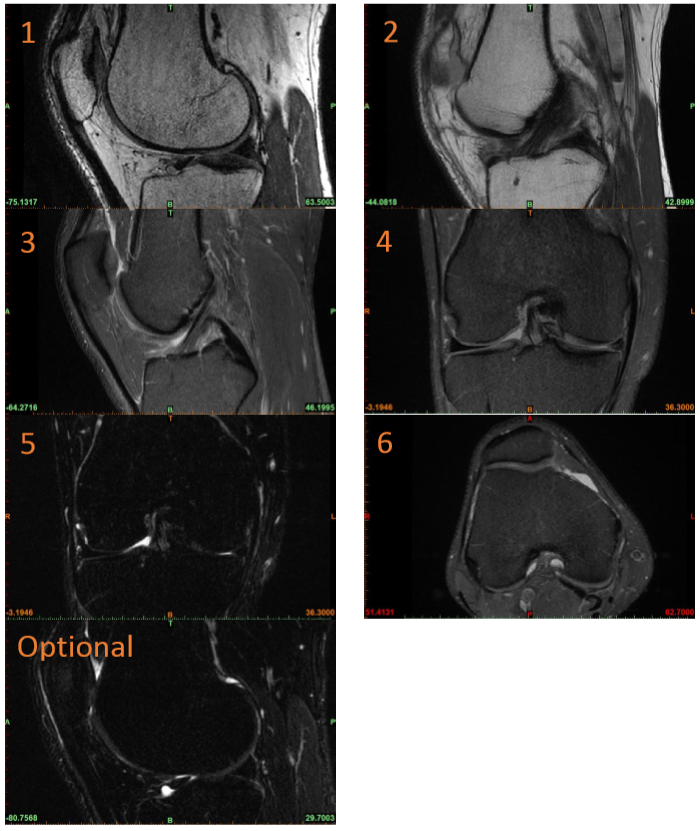

Mri Coronal Knee Planning . Check the planning block in the other two planes. An appropriate angle must be given in the sagittal plane, parallel to the midline of the femur and tibia. complete assessment of the knee requires that images be obtained in the sagittal, coronal, and axial planes. Place vitamin e tablet on skin lightly. magnetic resonance imaging (mri) of the knee is a common diagnostic. mr soft tissue mass. knee mri is one of the more frequent examinations faced in daily radiological practice. mri of the knee joint can lead to improved health outcomes by reducing (or eliminating) the need for diagnostic arthroscopy. plan the coronal slices on the axial plane, angling the planning block parallel to the medial and lateral condyle of the femur. three conventional mri planes that are utilized to evaluate the knee include sagittal (oblique), coronal, and transaxial planes. mri knee protocol comprises a group of mri sequences to routinely assess the knee for internal pathologies.